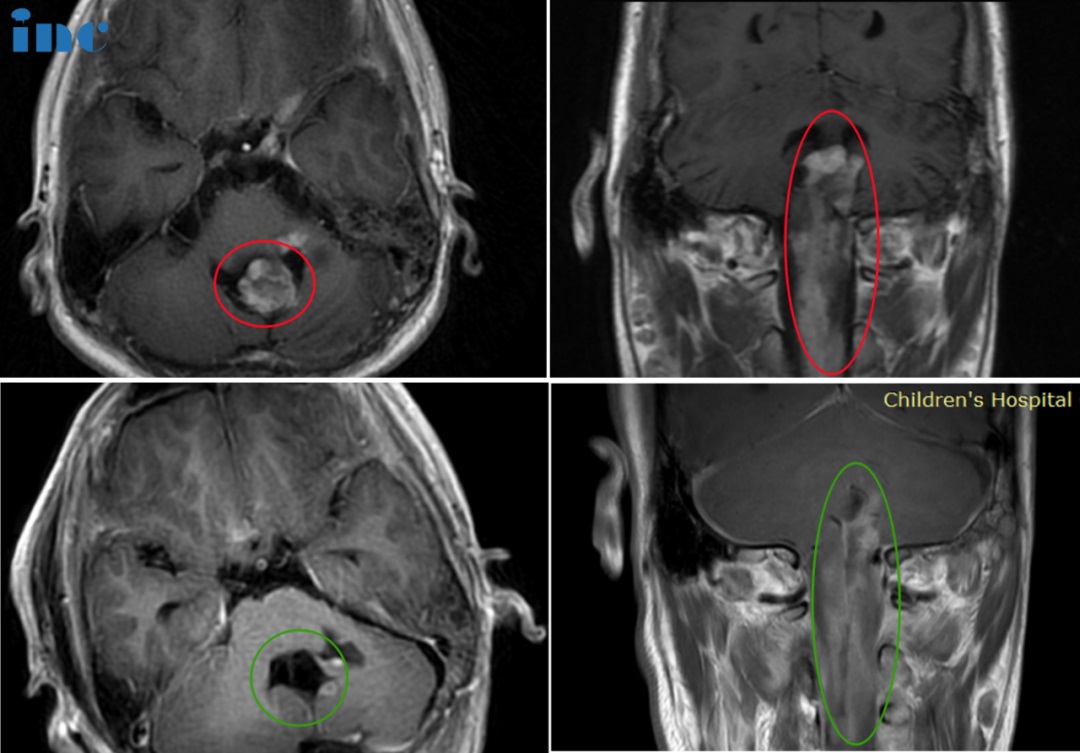

6岁男孩-延髓毛细胞星形细胞瘤

◉手术日期:2022年11月巴教授疑难示范手术期间

◉简要病史:患者于 2020 年 3 月到 4 月偶有吃饭时呕吐现象,未特别重视。2020年7月因外伤摔倒就诊当地医院,检查发现颅脑信号异常,进一步行磁共振检查,提示脑干占位性病变。2020年8月行导航引导下后颅窝占位切除术,术后医生表明肿瘤被全切。术后病理提示毛细胞型星形细胞瘤,KIAA1549-BRAF 融合基因阳性,WHOI级。术后无需辅助治疗,之后磁共振定期复查。2022年8月,磁共振复查提示肿瘤进展。9月磁共振复查较上次变化不大,但建议卡铂+长春新碱化疗,如果化疗效果不好再手术。父母考虑化疗对患儿副作用,暂时未行化疗。

◉治疗过程:2022年11月23日,在苏州大学附属儿童医院,巴教授顺利近全切天天的脑干-延髓毛细胞星形细胞瘤。

◉术后情况:术后三天查房交流清晰、肢体抓握能力正常、术后呼吸吞咽正常,食欲正常,可正常吃饭进食。

术后两个多月,孩子正常回归学校。

5岁女孩脊髓-脑干毛细胞星形细胞瘤

◉术前情况:5岁琦琦,右侧肢体无力伴有吞咽困难2月,伴有呕吐、头痛。无其他病史,北上多家医院辗转求诊。为了减轻脑积水,于某医院行右侧脑室腹腔内分流术,行MR提示脑干胶质瘤、脊髓胶质瘤,但是症状不见明显好转,加重趋势明显。如不手术,孩子将有生命危险。

◉治疗过程:此时正值INC巴特朗菲教授来华开展示范手术交流期间,琦琦一家得知巴特朗菲教授对于此类复杂疑难位置肿瘤有丰富的成功手术经验,于是选择咨询教授,教授回复至少可以切除95%以上的肿瘤,于是巴教授主刀在国内合作医院苏州大学附属儿童医院手术团队的配合下,肿瘤次全切(95%以上), 手术顺利,手术历时8小时。

INC巴特朗菲教授为琦琦手术中

◉术后情况:术后ICU留观1天,神志清楚,完全自主呼吸,拔除插管,生命体征平稳,转入普通病房。患儿右侧肢体活动度、肌力较术前明显好转。术后1周,患者下地自行行走,无手术并发症出现。术后3周出院,术后2月可如同龄患儿生活。他们一家人对INC以及巴特朗菲教授更是充满了感激,曾多次微信致谢。术后3年,琦琦可以像正常孩子一样玩耍。